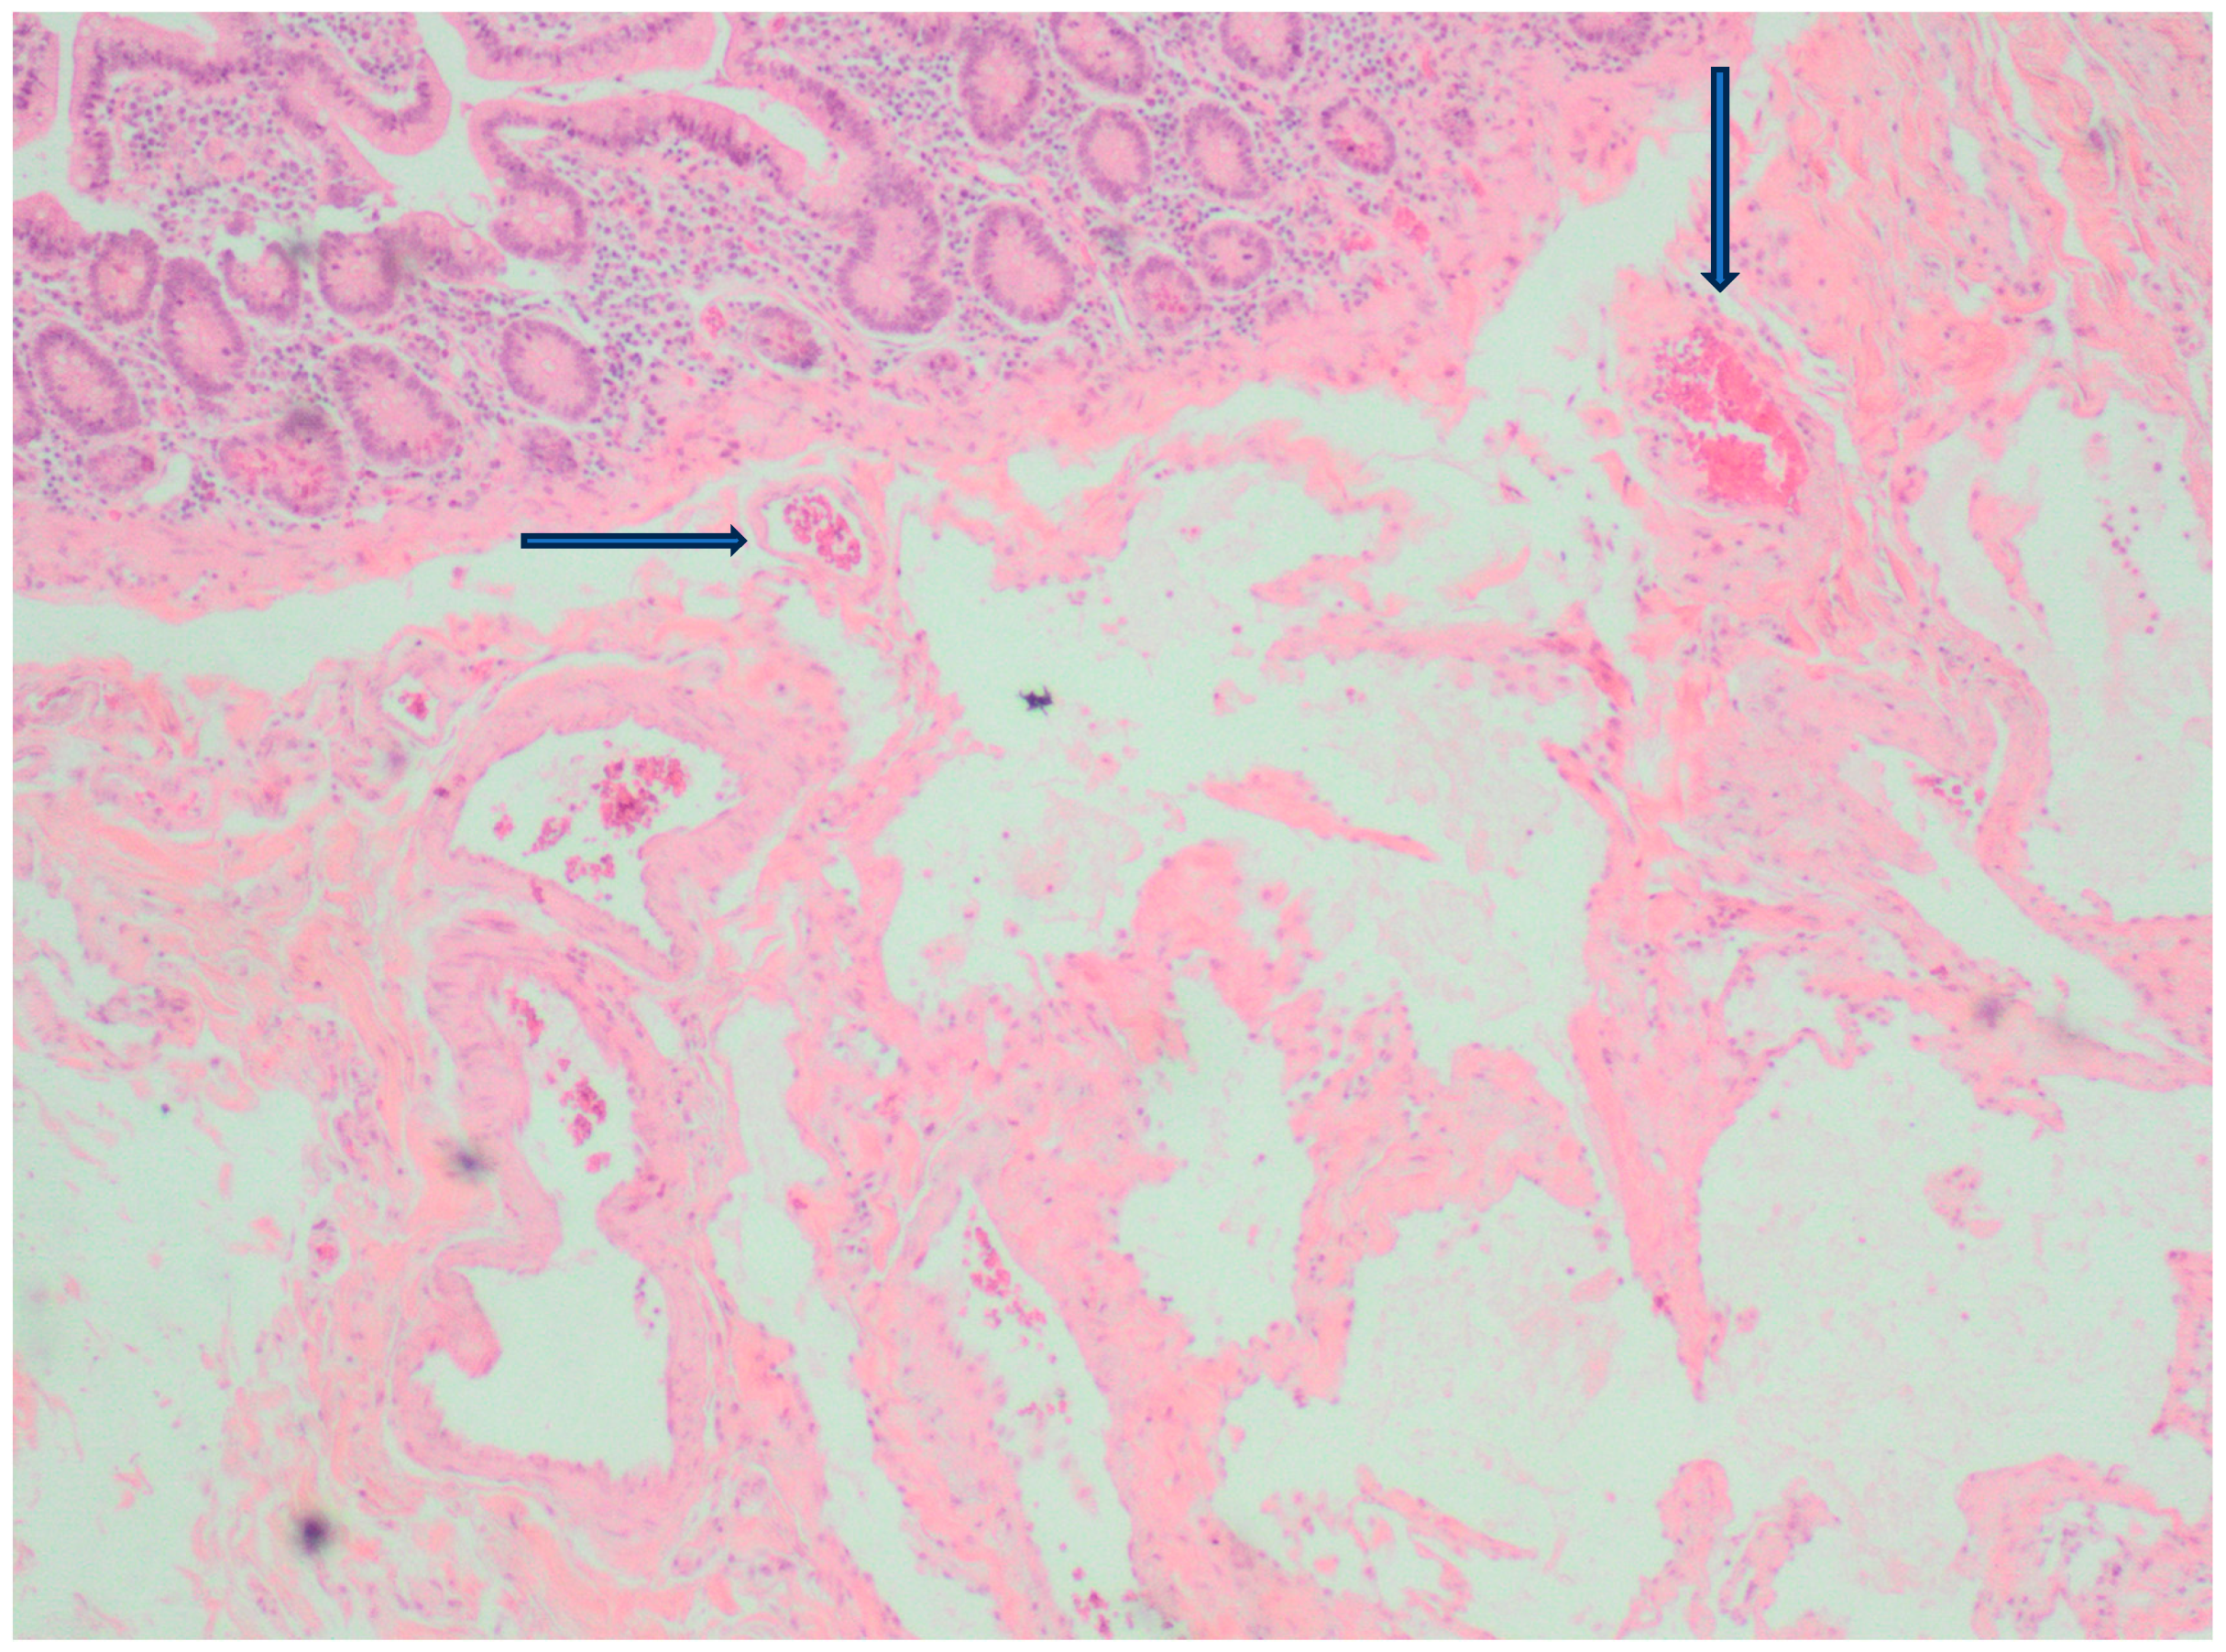

2. Case Presentation